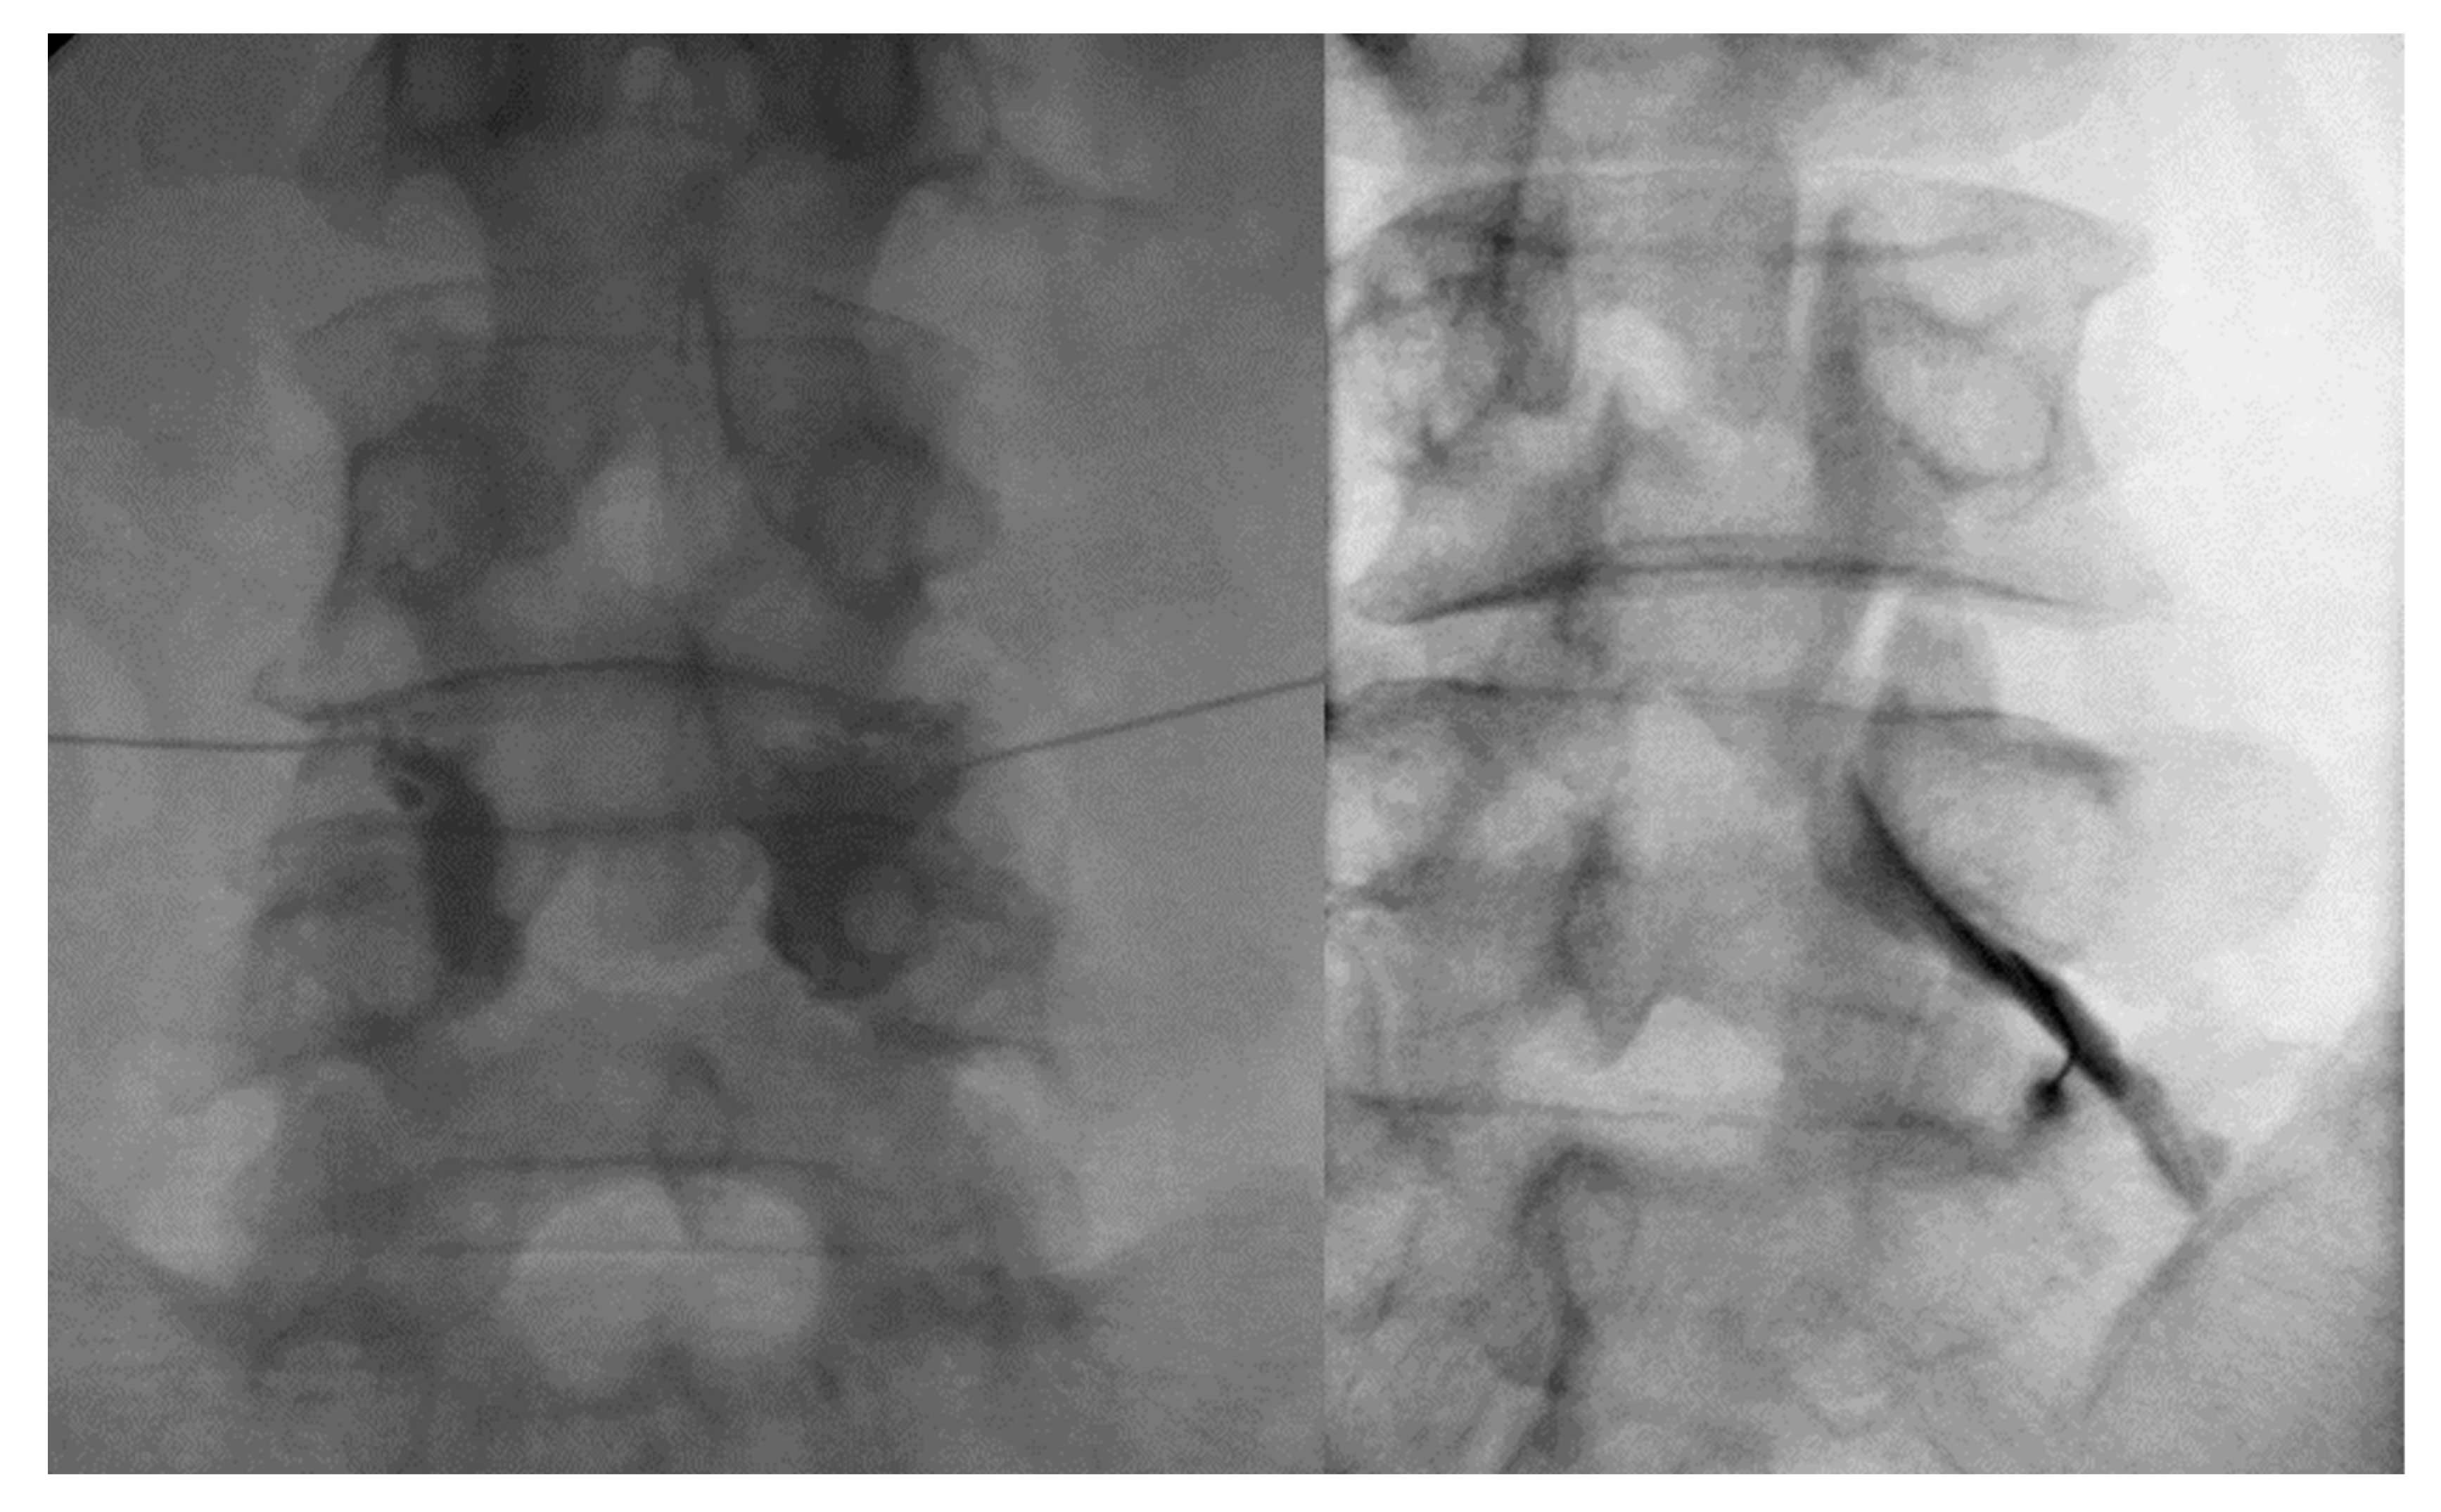

4.1. Facet Joint Injection Procedure